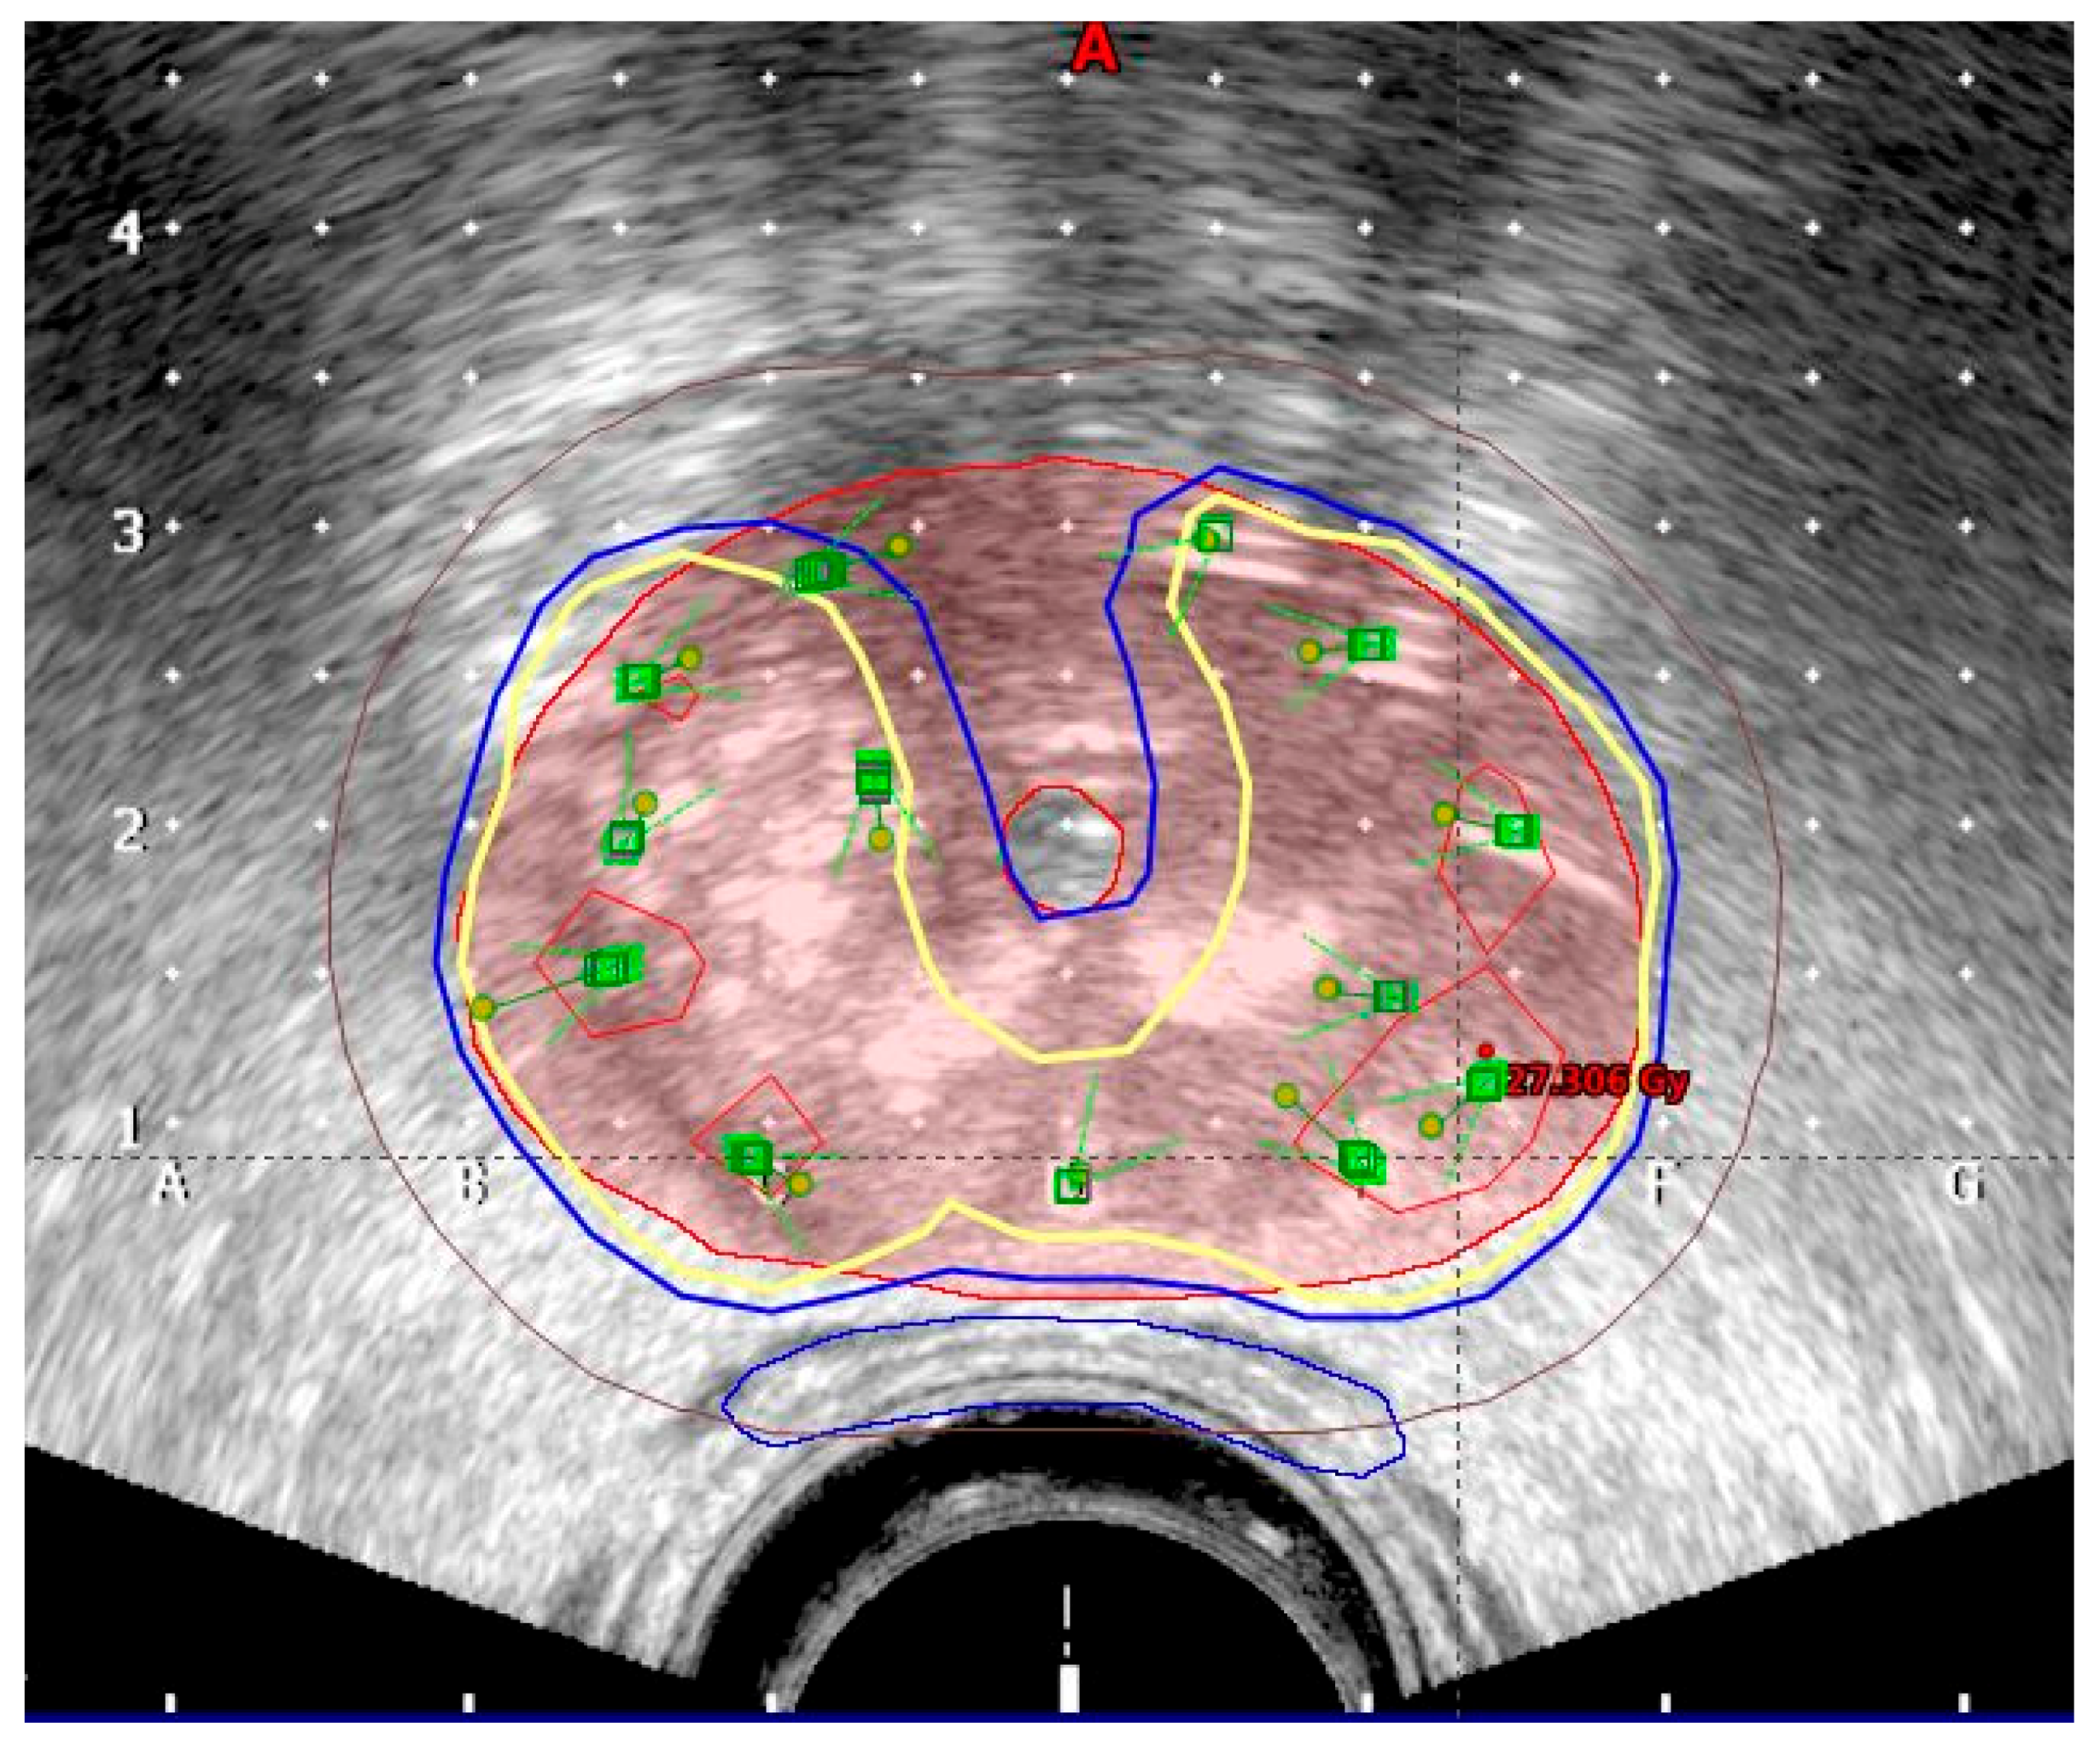

The planning target volume (PTV) was contoured by the radiation oncologist on each ultrasound slice and included the prostate with a 3 mm margin all around, except posteriorly, where no margin was given to avoid overdosing the anterior rectal wall. Superiorly, a margin of 5–7 mm was given to compensate for any post-implant edema and inadvertent caudal movement of the catheters in between the fractions. The PTV constraints were D90 (dose delivered to 90% of PTV) ≥ 97%, V95 ≥ 100%, and V150 ≤ 35%. Isodoses in transrectal ultrasound image are shown in Figure 1. A three-dimensional image with simulation of radiation is shown in Figure 2.

Figure 1.

Isodoses in transrectal ultrasound image (red: 15 Gy; yellow: 9 Gy; blue: 8 Gy; brown: 5 Gy).